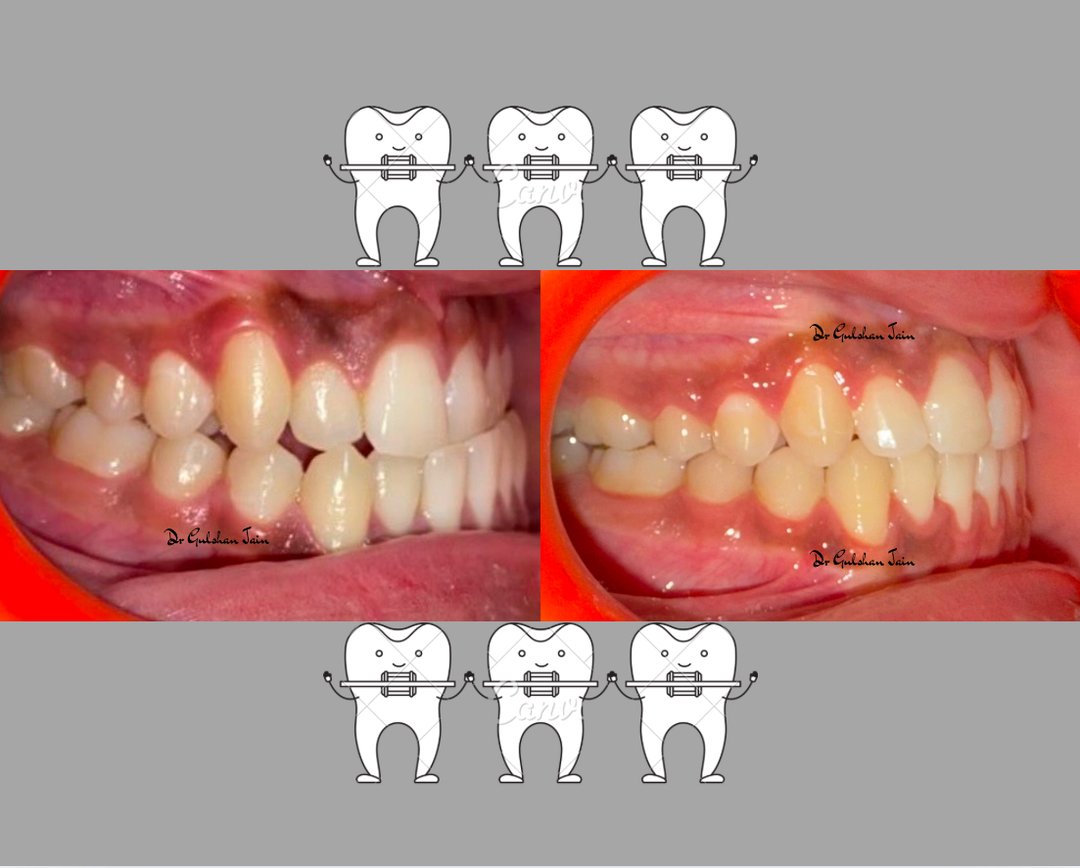

Welcome to our gallery

See how our company transforms ideas into reality. This gallery is a visual testament to our work and achievements.